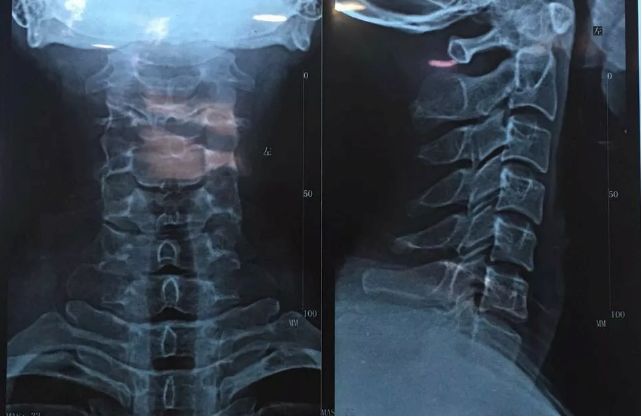

首先到医院进行确诊,体格检查+影像检查

影像检查就是通过仪器辅助检查,即拍片检查。